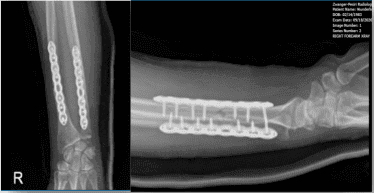

Hubo una sutil comintución: la fractura fue lavada a fondo. La reducción se hacía usando pinzas. La reducción fue un poco difícil teniendo en cuenta que la fractura era algo antigua. Una vez sostenida la reducción, se utilizó una placa de 8 orificios. Se fijó usando tres orificios distales y cuatro proximales.

Se fijó usando una combinación de tornillos de bloqueo y no bloqueo, logrando compresión en dos de sus tornillos proximalmente. Una vez completado el radio, se comprobó en el C-arm.

La atención se desvió hacia la fractura cubital. La exposición del cúbito se realizó mediante el acercamiento posterior sobre el cúbito. La fractura fue abierta y lavada. Hubo una cominúción de la fractura y un fragmento suelto.

La fractura se redujo y el fragmento suelto pudo colocarse en su lugar, y la fractura quedó bien reducida. La fractura se reparó usando una placa de 8 orificios y la combinación de tornillos de bloqueo y no bloqueo. Se usaron tres agujeros distales y cuatro proximales. Tras la reducción satisfactoria, se tomó y salvó la foto final.

Radiografía del antebrazo derecho – primera semana postoperatoria

Radiografía del antebrazo derecho – 16ª semana postoperatoria

Radiografía del antebrazo derecho – 32ª semana postoperatoria